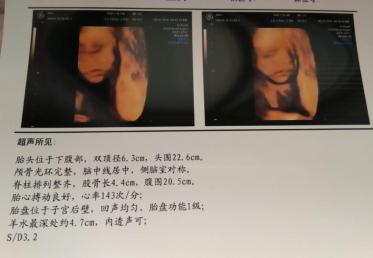

孕29周到孕32周,检测血压;孕33~34周,超声检查,评估胎儿大小和状态;孕35周到孕36周,综合判断胎儿情况,对分娩方式提出初步建议。